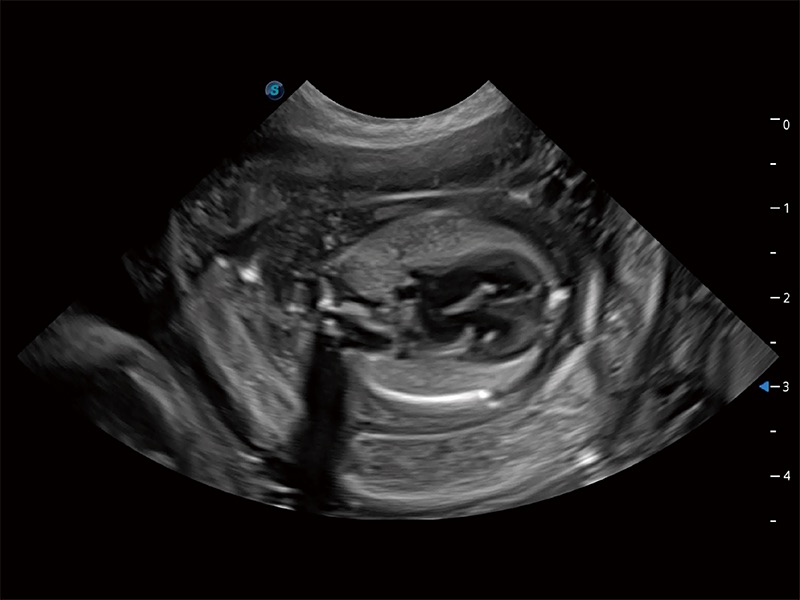

动物是人类最亲密的朋友和最值得信赖的伙伴。狗万官方网站也一直致力于探索动物专用的超声影像解决方案。全新推出的ProPet系列,是狗万官方网站在动物超声影像智能化、专业化、精准化的一次跨越式革新。动物不能用言语来表述自己的不适,通过超声影像,ProPet系列搭建了动物医生与不同物种沟通的“桥梁”,为动物医生注入了“治愈之力”。 ProPet 80 是狗万官方网站匠心打造的一款高端动物专用彩超,采用性能卓越的全新硬件架构,极大提升超声系统的运行效率和数据处理能力,帮助动物医生从容应对日益增多的挑战性病例和日益多样化的临床需求。

高性能和先进的临床应用工具可以为动物医生提供临床信心。ProPet 80 搭载了先进的腹部和浅表应用工具,帮助医生在日常临床实践中发挥前所未有的作用。

ProPet 80 专为动物医生设计,对不同的动物体型和生理结构作出了针对性的优化。通过动物影像专用软件,可满足个性化的应用需求,帮助动物医生获得更精确的诊断数据。

为精细结构及组织边缘提供高清晰度的图像和更大的成像视野。帮助减轻医生的用眼疲劳,快速精准获得测量的数据。